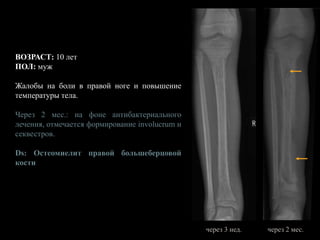

ВОЗРАСТ: 10 лет

ПОЛ: муж

Жалобы на боли в правой ноге и повышение

температуры тела.

Первоначальное рентгенологическое исследование

не выявило патологических изменений.

Ds: Остеомиелит правой большеберцовой кости

при поступлении

Через 3 нед.: очаги деструкции в

проксимальном и дистальном метафизах,

признаки линейного периостита

Ds: Остеомиелит правой большеберцовой

кости

при поступлении через 3 нед.

Через 2 мес.: на фоне антибактериального

лечения, отмечается формирование involucrum и

секвестров.

через 3 нед. через 2 мес.

Через 5 мес.: на фоне продолжающегося

антибактериального лечения, вокруг секвестра

выраженное формирование involucrum. Однако

секвестр остается потенциальным источников

инфекции, что требует проведения

секвестрэктомии.

Рост костей правой голени не нарушен, так как

эпифизарные пластинки большеберцовой кости

и малоберцовая кость интактны.

кости.

через 2 мес. через 5 мес.

Представленный случай является классическим

течением острого гематогенного остеомиелита с

изначальным отсутствием каких-либо

рентгенологических изменений с дальнейшей

хронизацией процесса с формированием

секвестров и последовавшей секвестрэктомией.

через 5 мес. после

секвестрэктомии